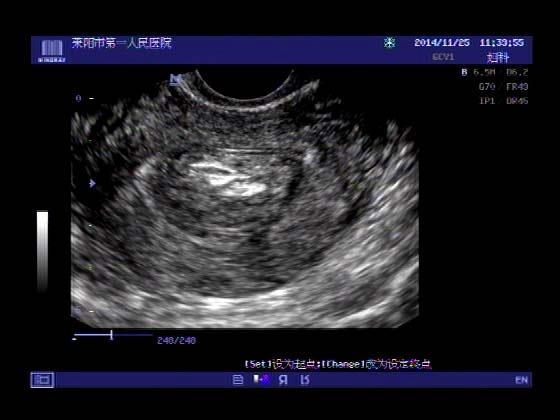

超声入门贴379---------粘膜下肌瘤(阴超的魅力)

女,43岁,月经量多3个多月,加重一个月

外院彩超检查提示:子宫后肌壁略高回声团------肌瘤?息肉?,盆腔少量积液

今天来我院检查:

巧妇难为无米之炊,经腹部超声确实很难定,阴超一目了然,乡镇医院诊断水平的提高更迫切的需要高档仪器的引进!